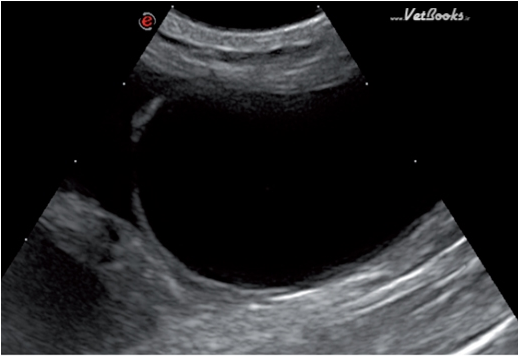

在有些腹腔内充满了自由液休,但膀胱没有破裂的病例中,可以看到因声波折射作用造成的部分膀胱壁看似缺失(图22)。在这样的病例中,膀胱通常是充盈的,膀胱壁厚度是正常的。可以与膀胱破裂相鉴别。